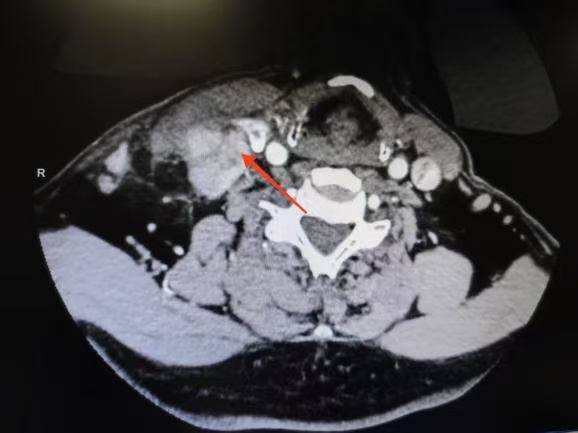

CT箭頭所示:右側(cè)甲狀腺腫瘤

荊楚網(wǎng)(湖北日報網(wǎng))訊(通訊員 楊青青 沈浩元 )近日,孝感市中心醫(yī)院甲狀腺乳腺外科成功為一名67歲男性患者實施了高難度甲狀腺癌根治手術(shù)。該患者因頸部突發(fā)硬塊4天就診,經(jīng)檢查確診為雙側(cè)甲狀腺乳頭狀癌伴右頸側(cè)區(qū)多發(fā)淋巴結(jié)轉(zhuǎn)移,術(shù)中進一步發(fā)現(xiàn)腫瘤已侵犯包繞喉返神經(jīng),側(cè)區(qū)轉(zhuǎn)移淋巴結(jié)亦侵犯頸內(nèi)靜脈,病情復(fù)雜且兇險。